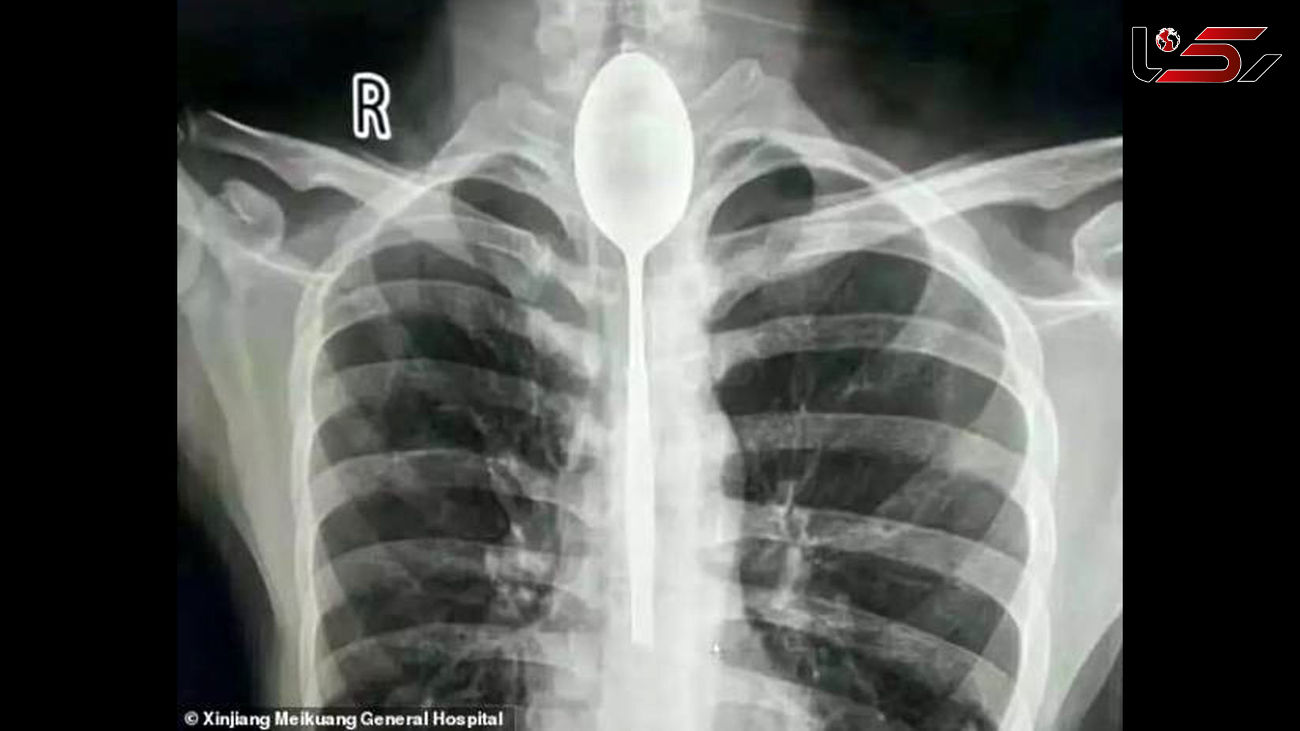

حوادث رکنا: یک مرد چینی قاشقی را قورت داد و قاشق یک سال در گلوی او بود.

به گزارش رکنا،یک مرد چینی یک سال زندگی خود را در حالی سپری کرد که یک قاشق در گلو ی او گیر کرده بود.

مرد چینی در یک شرط بندی احمقانه قاشق 20 سانتی را بلعید و از آنجایی که مشکلی در خوردن و آشامیدن نداشت تا یکسال این قاشق داخل گلوی وی ماند.

مرد چینی قاشق فلزی 8 اینچی را به عنوان یک شیرین کاری احمقانه در سال گذشته بلعید. قاشق در مری او گیر کرد، اما چون به راحتی می توانست بخورد و بنوشد، هرگز به دنبال کمک پزشکی برای بیرون آوردن آن نبود. او می گوید تنها چند روز پیش به علت ضربه وارد شده به قفسه سینه ، دچار درد قفسه سینه شد.

مردی که نامش فاش نشده است از منطقه جین جیانگ چین به پزشکان گفت :او یک قاشق فولادی ضد زنگ را در طی یک شرط درحالت مستی بلعیده . او به دوستانش گفته که می تواند قاشق را ببلعد و بعد دوباره با ریسمانی که به دسته قاشق می بندد آن را بیرون آورد . در آن زمان برای او حتما فکر خوبی به نظر می رسید، اما همه چیز طبق برنامه پیش نرفت و قاشق در گلوی او گیر کرد. به جای رفتن به بیمارستان، مرد منتظر ماند تا ببیند آیا قاشق به طور عادی از خوردن و نوشیدن جلوگیری می کند یا نه ؛ این طور نبود، پس در مری ماند تا سال گذشته.

قاشق مدت طولانی در سینه او مانده بود و براثر ضربه ای که به سینه او وارد شده بود باعث درد شدید و تنفس بدبو او شده بود . سرانجام به بیمارستان عمومی جین جیانگ رفت و به پزشکان گفت یک سال است که قاشق فلزی در مری او گیر کرده است.

دکتر یو در بیانیه ای که توسط بیمارستان منتشر شد ، نوشت:من هرگز چنین چیزی ندیده ام ؛ شوکه شده بودم.

پزشکان در بیمارستان عمومی جین جیانگ پس از بحث در مورد بهترین مسیر عمل تصمیم گرفتند که بهترین راه خارج کردن قاشق ، از طریق دهان بوده است. داروی بی هوشی به بیمار دادند و یک تیم دو ساعت تلاش کردند تا با استفاده از تجهیزات آندوسکوپی ، قاشق 8 اینچی را بیرون آوردند.